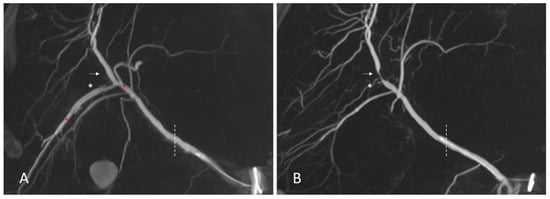

3.2. Vascular Findings—Anatomic Variants and Pre-Existing Pathologies of the Hepatic Vasculature

3.3. Analysis of Types and Occurrences of Arterial Complications